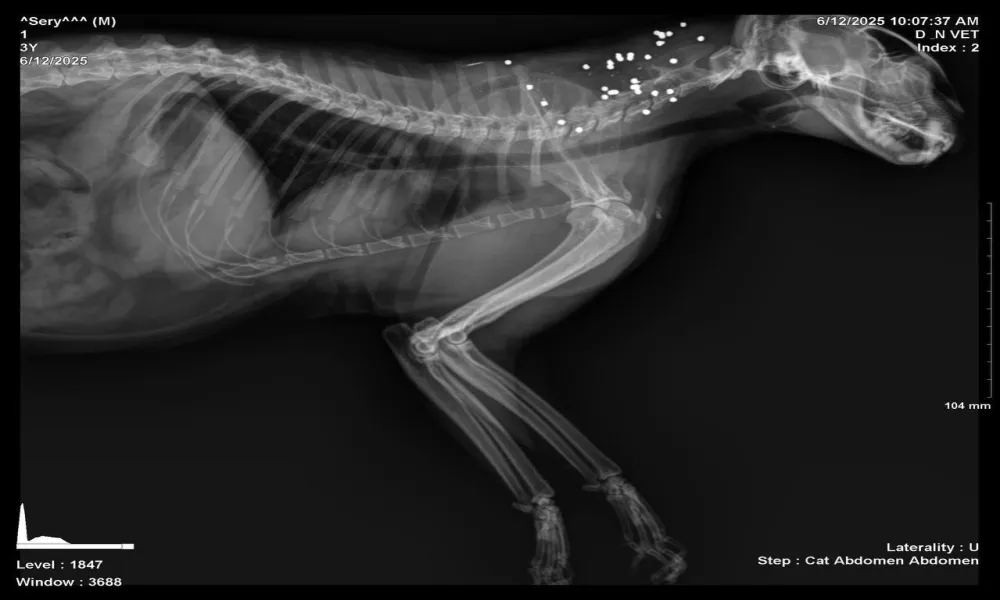

Στην επαρχία Πάφου, το Κίνημα αναφέρεται σε δύο ξεχωριστές περιπτώσεις. Στην πρώτη, γάτος εντοπίστηκε στις 16 Φεβρουαρίου 2026 πυροβολημένος και παράλυτος. Με βάση την ανακοίνωση, οι ακτινογραφίες κατέδειξαν την ύπαρξη σφαίρας στο σώμα του ζώου, το οποίο τελικά οδηγήθηκε σε ευθανασία. Στη δεύτερη περίπτωση, σε άλλο γατάκι εντοπίστηκαν πολλαπλά σφαιρίδια στο σώμα του.